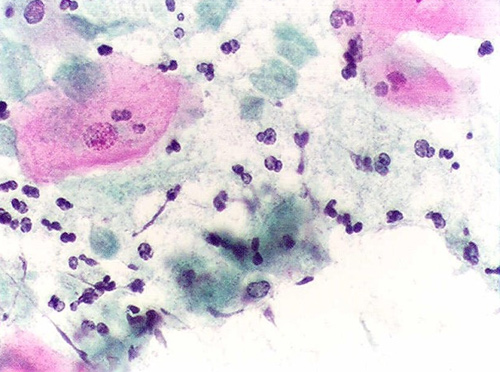

08/11/2018 13:57Nấm Candida sinh dục

Bệnh viêm âm hộ, âm đạo do nấm rất thường gặp ở phụ nữ, nó đứng thứ 2 sau viêm âm đạo do vi khuẩn và thường cao gấp 3 lần bệnh trùng roi âm đạo. Có tới trên 50%, thậm chí có người cho rằng tới 3/4 số phụ nữ mắc bệnh này ít nhất 1 lần trong cuộc đời.

Nguyên nhân gây bệnh chủ yếu do Candida albicans chiếm khoảng 90%, ngoài ra còn có các chủng Candida khác. Nhiều phụ nữ bị nhiễm nấm nhưng không có biểu hiện bệnh, khi gặp điều kiện thuận lợi như vệ sinh kém, mặc quần áo quá chật, ẩm ướt và không thoáng khí dễ có biểu hiện bệnh lý. Khi mắc bệnh, người phụ nữ thường có hai triệu chứng nổi bật là rất ngứa và ra khí hư. Triệu chứng ngứa âm hộ là thường gặp nhất và làm cho người bệnh rất khó chịu, nhiều người gãi gây trầy xước làm bội nhiễm tại chỗ. Khí hư thường không nhiều và có màu trắng như váng sữa, không có mùi hôi. Các biểu hiện khác là đau, cảm giác bỏng rát trong âm đạo, âm hộ, đi tiểu khó và đau khi giao hợp. Trường hợp nặng có thể gây đỏ, phù nề âm hộ và môi nhỏ, môi lớn, đôi khi lan ra cả đùi, bẹn. Bệnh thường nặng lên trước kỳ kinh nguyệt.

Đàn ông khi quan hệ tình dục với phụ nữ bị bệnh cũng có thể bị viêm quy đầu, bao quy đầu bị đỏ, ngứa, cảm giác bỏng, rát và có chất nhày trắng. Bệnh thường xảy ra vài phút hoặc vài giờ sau khi giao hợp và thường khỏi sau khi rửa sạch.

Hiện nay có rất nhiều loại thuốc mới có hiệu quả điều trị cao dùng đặt tại chỗ hoặc uống. Tuy nhiên, chị em cần lưu ý việc vệ sinh tại chỗ, giữ cho vùng sinh dục không bị ẩm ướt, không mặc đồ quá chật, chất liệu nhiều nilon...

Theo BS. Nguyễn Duy Hưng (Sức Khỏe & Đời Sống)